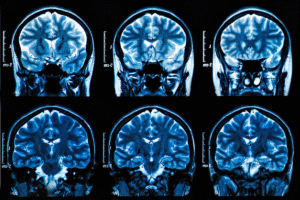

MS and Parasites Cause Brain Lesions

Revealing the Overlooked Link Between Parasitic Infections and Multiple Sclerosis A New Perspective on Multiple Sclerosis For decades, people diagnosed with multiple sclerosis (MS) have been told that their immune system is attacking their body for no reason — that it’s an autoimmune disease with no known cause and no cure. But new research tells

Is Multiple Sclerosis a Vascular Disease—Not an Autoimmune Mystery

For decades, multiple sclerosis (MS) has been treated as an autoimmune disease where the immune system attacks nerves for no clear reason. Groundbreaking research over the last several years is rewriting that story. Today, leading evidence points to MS as primarily a vascular disorder: a disease driven by chronic blood-vessel dysfunction, low oxygen, impaired venous